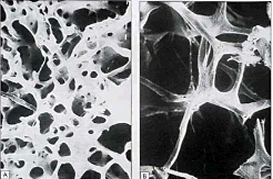

DEXA bone densitometry is most often used to diagnose osteoporosis, a condition of gradual loss of calcium, causing bones to become thinner, fragile, and more likely to break. Post-menopausal women are often affected, but it may also be found in men. Heredity has been shown to be a significant indicator for developing the disease.

Densitometry is today’s established standard for measuring bone mineral density most commonly by viewing the lower spine and hips. Visalia Women's Imaging Specialists uses the Hologic brand unit which is known for a high level of accuracy. This is a quick, painless procedure for measuring bone loss and contrast injection is not required. The results are interpreted by the radiologist using two scores: The "T" score number shows the amount of bone you have compared with a young adult of the same gender with peak bone mass. The “Z” score reflects the amount of bone you have compared with other people of comparable age, size and gender.